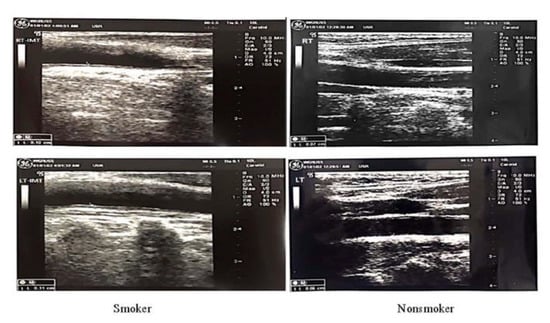

The means of blood HDL and LDL cholesterol were lower in the blood of smokers than in non-smokers, whereas the TC, TG, the TC/HDL-C ratio and IMTs of the two corresponding carotid arteries were increased (Table 2). Significant increases in the RCA and LCA’s thickness were noted, whereas the other variations were insignificant (see Table 2 and corresponding Figure 1).

Figure 1. Increase in the thickness of the RCA and LCA.